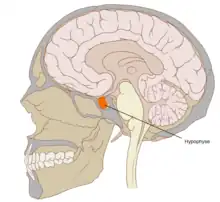

| Pituitary | |

A pituitary disease is a disorder primarily affecting the pituitary gland.[1]